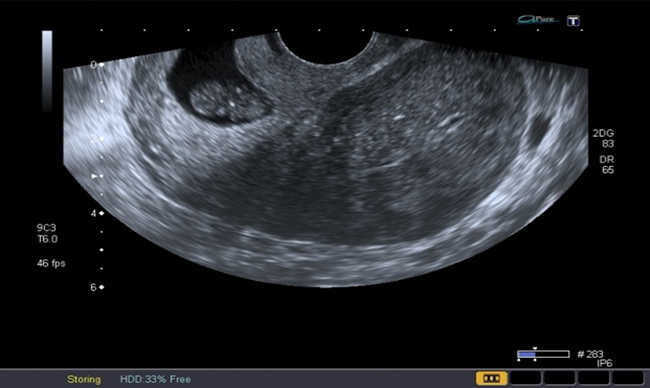

A la paciente se le realizó una prueba en sangre para cuantificar la fracción beta de la gonadotrofina coriónica humana (Abbott Laboratories. Architect.B-hCG Total), que se reportó en 31.819 mUI/ml. También se le tomó una ecografía endovaginal (Toshiba-Xario XG) que mostró la presencia de útero con medidas de 72 × 52 × 54 mm con un cuello de 35 mm con orificio interno cerrado. El endometrio midió 18 mm, sin evidencia de saco gestacional intrauterino y en la región ístmica y cervical, por debajo de las arterias uterinas, se encontró un saco gestacional de 30 mm con presencia de embrión único de 20,6 mm sin presencia de actividad cardiaca fetal (figuras 1 a 4).

Figura 1 Presencia de cavidad uterina vacía, con endometrio sin presencia de saco gestacional. Presencia de saco gestacional cervical